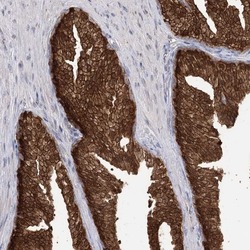

Supportive validation

- Submitted by

- Invitrogen Antibodies (provider)

- Main image

- Experimental details

- Immunohistochemical analysis of R3HDM2 in human prostate using R3HDM2 Polyclonal Antibody (Product # PA5-58346) shows strong cytoplasmic and nuclear positivity in glandular cells.